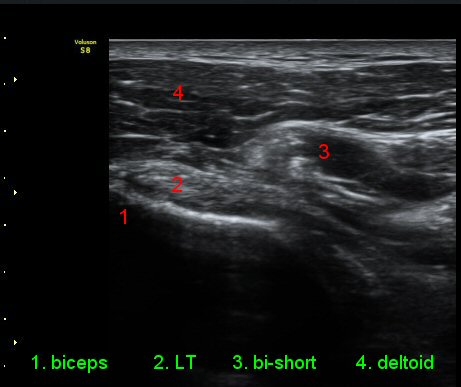

ÆÈÀ» ¿ÜȸÀüÇÏ´Ï °ß°©ÇÏ±Ù°Ç Ç¥ÃþÀÇ ¼ö¾×Àú·ù°¡ ´õ¿í È®½ÇÇÏ°Ô °üÂûµµ´Ï´Ù(»çÁø 4).